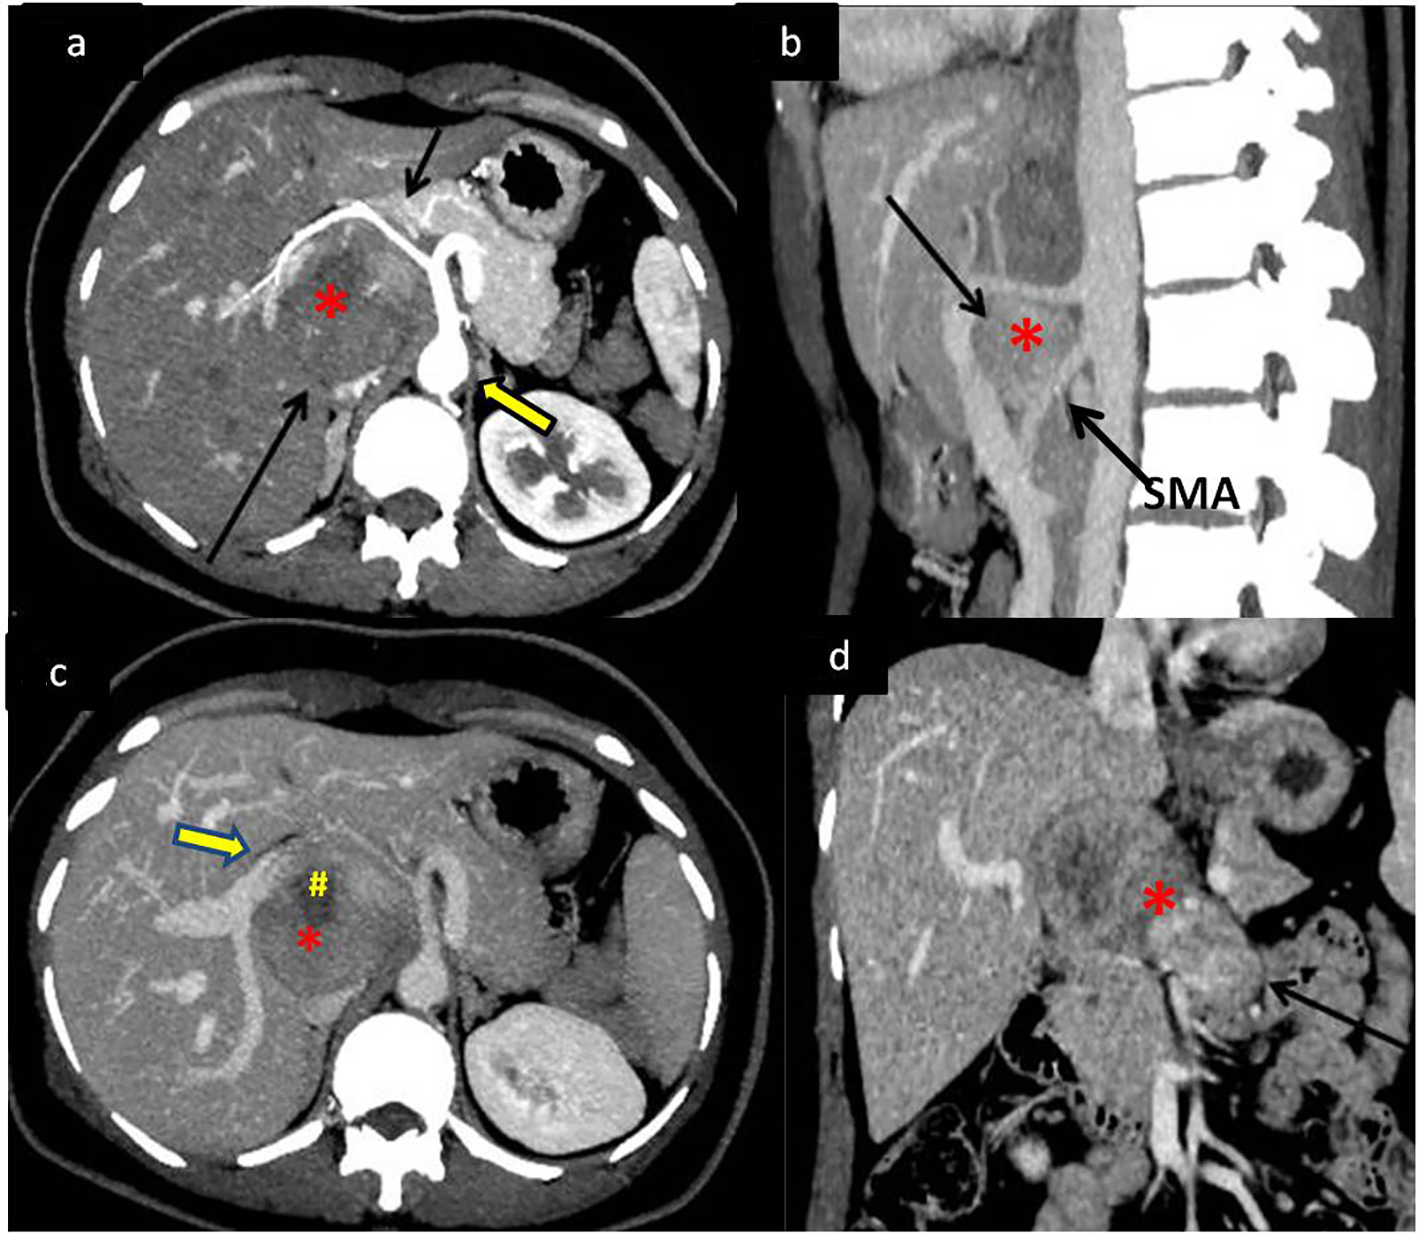

A 43-year-old female presented to our hospital with the complaints of progressive pain abdomen for 3 months. Abdominal pain was unrelated to food intake and was constant, dull-aching in nature. No lump was palpable on clinical examination and the abdomen was non-tender. Laboratory investigations including hematological and liver function tests were normal. On the basis of the above physical assessment, the patient was referred for cross-sectional imaging- sonography of the abdomen, to evaluate the cause of pain. The investigation revealed a hypoechoic retroperitoneal mass sandwiched between the pancreas anteriorly and the aortocaval region posteriorly, encasing the origin of common hepatic artery (Fig. 1a, b). The patient further underwent a contrast-enhanced computed tomography (CECT) scan on a 64-slice CT scanner (Discovery750HD, General Electric, GE Healthcare, USA) to characterize the mass. CECT was performed by injecting 100 mL of intravenous contrast iomoperol (Iomeron, Bracco, Germany) using a pressure injector with bolus tracking technique and a dynamic triple phase study through an 18-gauge needle in the ante-cubital vein at a rate of 4 mL/s. In addition to a baseline non-contrast study, images were acquired during arterial phase (20 s), venous phase (70 s) and equilibrium phase (180 s). Thin reformatted and multiplanar images were studied before arriving at a differential diagnosis for the mass. The above CECT scan revealed a heterogeneously enhancing, lobulated solid mass lesion in the retroperitoneum with internal non-enhancing liquefied/necrotic areas anterior to the aortocaval region. The enhancement was persistent but equivalent to the phase of the dynamic study. The mass was seen to encase the celiac axis and its branches at their origin with extension along the common hepatic artery (CHA) for a small segment after origin (Fig. 2a) and along the hepatoduodenal ligament towards porta hepatis. It was seen to abut and partially encase the superior mesenteric artery (SMA) with circumferential contact of 180° (Fig. 2b) as well as compress and displace the main portal vein (Fig. 2c). The mass was seen to cross the mid line towards the left side in the pre-aortic location (Fig. 2d). Mass effect on the common duct was present with resultant minimal central bilobar intrahepatic biliary radicles dilatation. Fat planes with other neighboring structures such as caudate lobe of liver, right adrenal gland and the inferior vena cava (IVC) were maintained. There was no evidence of calcification within the tumor bulk. Based on the above features of soft tissue extension and insinuation along the retroperitoneal structures and partial encasement without obvious thrombosis of the affected vessels within the abdomen, a differential diagnosis of lymphoma or retroperitoneal mesenchymal tumor was made.

![]() Click for large image | Figure 2. Dynamic contrast-enhanced CT (CECT) scan to determine extent of mass with vascular and neighboring structures involvement. (a) CECT in the arterial phase showing the soft tissue retroperitoneal mass (*) (bottom black arrow) anterior to the aorta (bold arrow) splaying and encasing the common hepatic artery (top black arrow). (b) Sagittal maximum intensity projection (MIP) reformatted image of the mass (*) splaying the celiac axis and superior mesenteric artery (SMA) at origin (arrow). (c) Portal venous phase of the dynamic CECT showing mass (*) displacing portal vein (bold arrow) anteriorly with areas of necrosis (#) within it. (d) Coronal reformat showing the mass (*) extending across the midline of the abdomen (arrow). |

Till date, only 60 cases of primary EGIST of the retroperitoneum have been reported so far [3]. The objective of presenting our case of primary retroperitoneal EGIST was to highlight its clinical presentation and imaging characteristics along with the disease course showing rapid progression despite aggressive imatinib therapy. In our patient, the clinical onset of disease was insidious over a period of 3 - 4 months with increasing abdominal pain, since the mass was extraluminal in location. The pain was likely due to the neuro-vascular encasement by the mass as demonstrated in the retroperitoneum (Figs. 1a and 2a).

Extra-gastrointestinal tumors present as soft tissue complex masses with variable degrees of cystic fluid, liquefaction, necrosis and hemorrhage within the tumor bulk that would appear typically as hypoechoic or anechoic areas within an echogenic soft tissue mass on sonography and as hypoattenuating areas interspersed within an enhancing mass on contrast CT/MRI scan. Similar imaging features may be seen in lymphomas and other mesenchymal tumors in the same location; however, the differentiation from EGISTs on imaging may be made on the basis of absence of necrosis, cystic changes, hemorrhage and calcification within lymphomatous neoplasms [19, 20]. Even though the tumor in our case did not demonstrate any calcification within it, calcification within these tumors has been described in few reports in literature [4, 6]. Calcification is rare in untreated lymphoma of the retroperitoneum [21]. The tumor size in our patient was less than 10 cm in its largest dimension, which is an interesting observation compared to large malignant GISTs (average size more than 7 cm) in previously demonstrated studies [3, 4, 22]. No other metastatic lesion was demonstrated on imaging. Secondary deposits in primary retroperitoneal EGISTs are rarely reported [11]. The above imaging features in a case of retroperitoneal mass lesion with internal soft tissue homogeneity and vascular encasement should prompt the radiologist to think of EGIST as a possible differential diagnosis. The endoscopic ultrasound guided fine needle aspiration cytology and cell block preparations revealed predominantly spindle cell histological pattern in our patient. The two main patterns of histology, demonstrated by retroperitoneal EGISTs, are spindle cell and epithelioid variety, showing predominantly cigar-shaped and polygonal cells, respectively [11, 12]. The lesion demonstrated classical c-kit (CD117) positive features on IHC.